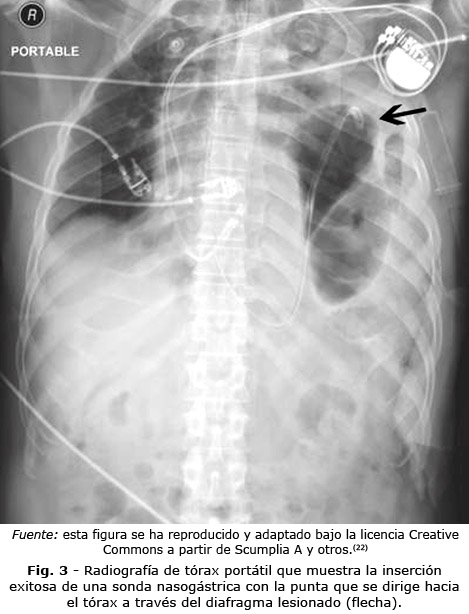

La mayoría de los signos radiográficos de ruptura diafragmática son indirectos, ya que evaluar la continuidad de esta estructura por este método es difícil. Algunos datos orientativos son los cambios en la silueta diafragmática dados por pérdida de la convexidad normal o una elevación de 4 a 6 cm por encima del hemidiafragma contralateral.(10) Dentro de los signos más específicos se encuentra la presencia de niveles hidroaéreos en el tórax que puede corresponder al intestino o estómago herniado a través del diafragma. La presencia de la porción terminal de una sonda nasogástrica en el tórax también suele orientar el diagnóstico (Fig. 3).(21)

Es importante resaltar que los hallazgos mencionados se presentan con mayor frecuencia en el trauma cerrado. Las lesiones diafragmáticas generadas por trauma penetrante suelen ser pequeñas y la herniación aguda en estos defectos es infrecuente.(23) Otro aspecto para tener en cuenta es que, la presencia de derrame pleural, contusión pulmonar y atelectasias pueden disminuir la sensibilidad de la radiografía simple.(10)